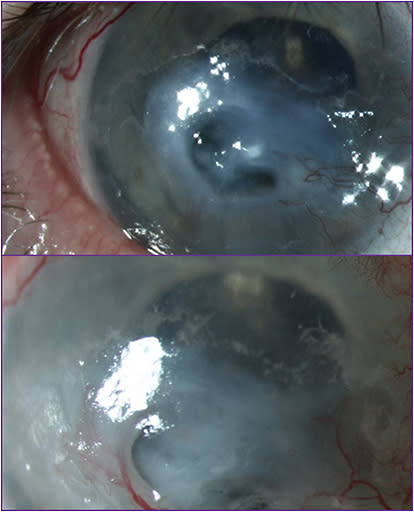

This 65-year-old man has severe rheumatoid arthritis and a history of bilateral retinal detachments, bilateral silicone oil, with history of vitrectomy and bilateral silicone oil, with a scleral buckle on the left eye. He’s had multiple amniotic membranes placed after perforations.

The patient has a long history of noncompliance with prescribed medications, including methotrexate and oral prednisone, and he has repeatedly been lost to follow-up over a period of years. His vision is counting fingers in both eyes.

The patient has experienced perforations in both eyes. Figure 7 (top) shows the right eye when the patient had a descemetocele and (bottom) after amniotic membrane placement to treat the thinning cornea. The patient has received multiple amniotic membranes and several courses of cenegermin-bkbj.

Patients with systemic autoimmune and inflammatory diseases can be particularly challenging to diagnose and treat. It’s important to check corneal sensation in both eyes, as these patients likely have bilateral neurotrophic keratitis.